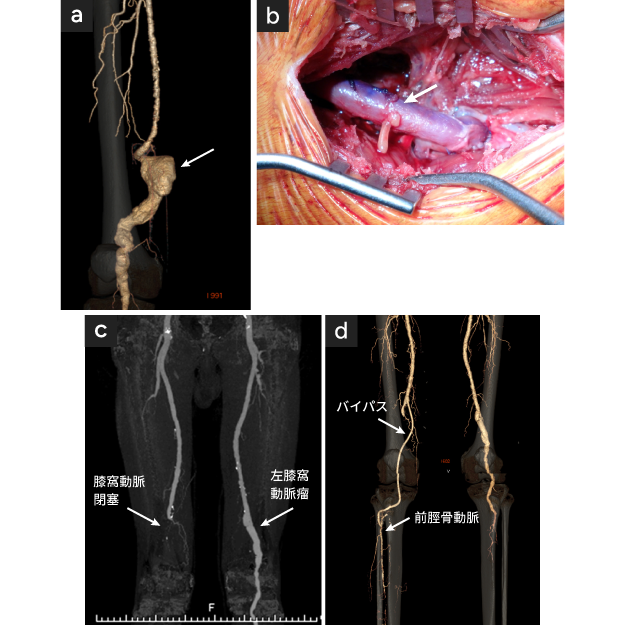

図1

図1. 右膝窩動脈瘤

• 【血管造影所見】膝窩動脈瘤(矢印)

• 【治療】膝窩動脈瘤切除、自家静脈置換術(矢印)

• 【血管造影所見】右膝窩動脈が急性閉塞

• 【治療】緊急右膝上膝下動脈-前脛骨動脈バイパス術により下肢救済